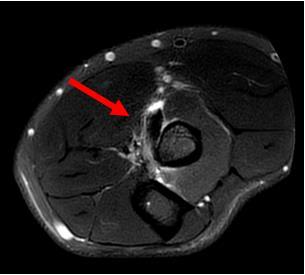

Fig. 7 Axial MRI showing rupture of the distal biceps. The tendon is absent from the radial tuberosity (red arrow). The bicipital aponeurosis has also torn causing subcutaneous and deep fascia oedema over the medial forearm (blue arrows). OTHER DISTAL BICEPS PATHOLOGIES

Fig. 9 Axial MRI showing thickened biceps tendon with fluid in the surrounding bicipitoradial bursa (red arrow).